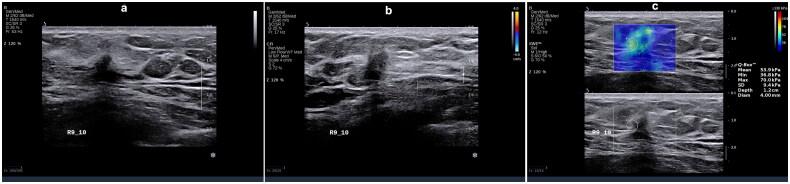

We performed a retrospective analysis encompassing 310 young women with breast cancer. Observations were made regarding the ultrasonography and elastography characteristics of the identified breast lesions. Subsequently, based on immunohistochemistry results patients were classified into five distinct molecular subtypes: luminal A, luminal B (HER2-), luminal B (HER2+), HER2+, and triple-negative breast cancer (TNBC). Clinical, pathological, and ultrasound imaging features were compared among these subtypes using binary logistic regression analysis.

Statistically significant differences were observed in various parameters across the five molecular subtypes ( < 0.05), including tumor size, morphology, margins, calcification, posterior echo features, blood flow (Adler grading), and tumor hardness. Specifically, luminal A subtype exhibited propensity for spiculated margins, lower blood flow grading, and decreased hardness; luminal B subtype was characterized by angular margins; HER2+ subtype manifested higher blood flow grading, calcification, and elevated hardness. Conversely, TNBC subtype displayed smooth margins, absence of calcification, and heightened hardness.

Specific molecular subtypes of breast cancer have unique ultrasonic and elastic imaging characteristics.